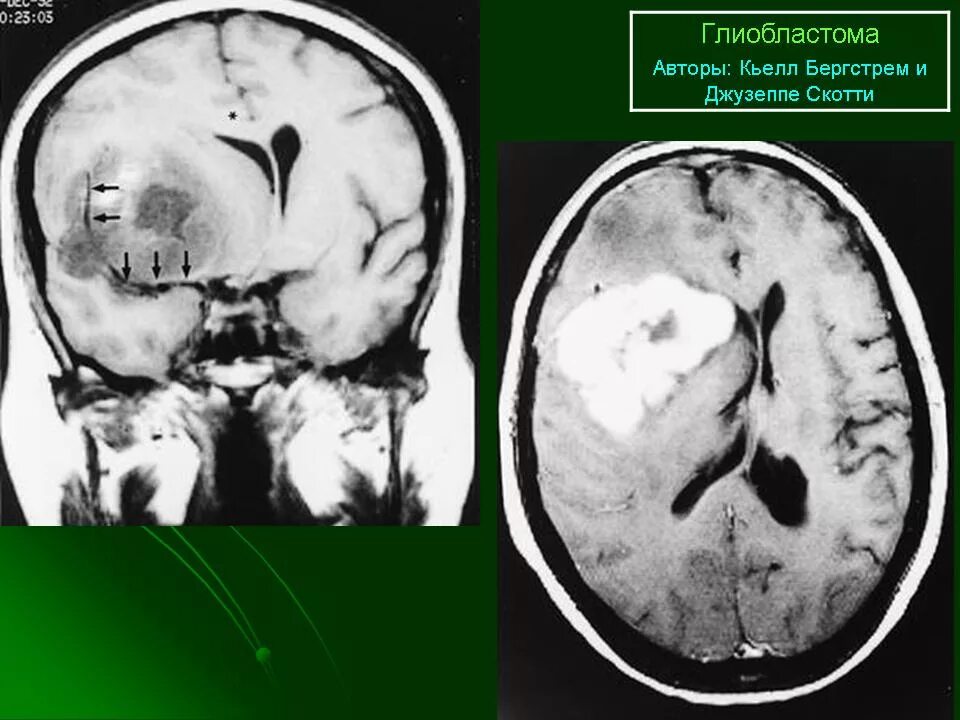

Мрт симптомы